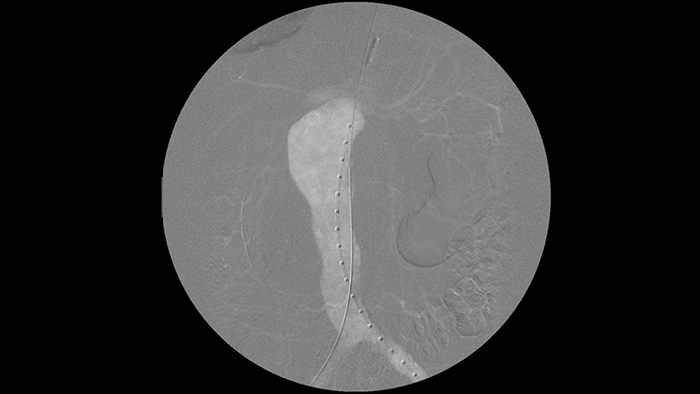

Tratamiento vascular

La angiografía por sustracción digital (ASD) se utiliza en procedimientos vasculares intervencionistas para ver con claridad los vasos sanguíneos mediante la eliminación de estructuras que pueden oscurecer la visibilidad de los vasos. La hoja de ruta de fluoroscopia superpone la imagen de contraste sustraída con anterioridad adquirida en la fluoroscopia en vivo, lo que le permite rastrear el dispositivo sin reinyectar el contraste.

Utilice la herramienta de contorno para marcar con facilidad una bifurcación o las ramas laterales solo dibujando en el monitor de la estación de visualización móvil con el dedo o con un ratón conectado externamente.

Opciones de contraste de yodo y CO2

Mejore la visibilidad de la vasculatura tortuosa con opciones de medios de contraste de yodo y CO2. Controle fácilmente las inyecciones desde la mesa. Para los pacientes con insuficiencia renal, puede utilizar la opción de CO2 para ver con facilidad los vasos pequeños sin usar contraste de yodo.